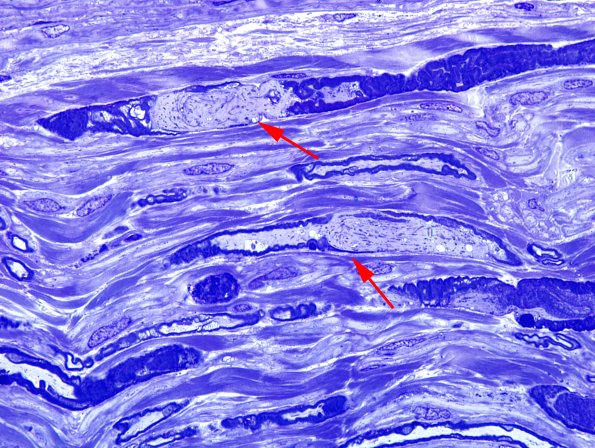

Crush artifact in this longitudinal section. The myelin sheath is disrupted in a patchy fashion (arrows) which likely explains the appearance of “half myelination” to be discussed in images #16A1-4. (Toluidine blue stained one micron thick plastic embedded sections)